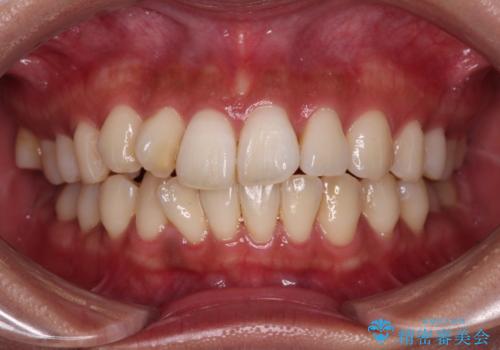

ワイヤー矯正後の後戻り 出っ歯を治したい マウスピース矯正